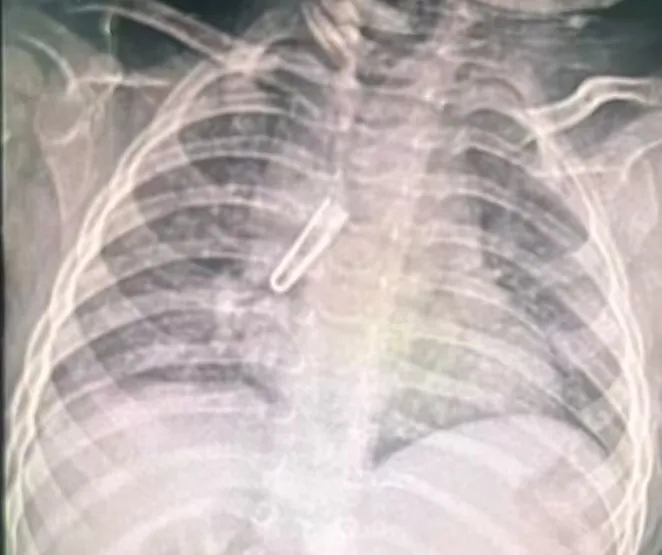

婴儿来院时肺部CT影像

1月6日深夜,一场与时间赛跑的生命救援在焦作市人民医院紧急上演。一名仅11月22天大的女婴不慎误食绳子上的铁皮卡扣,当地医院胸片确诊气管异物后,于当晚11点紧急转诊至焦作市人民医院儿科二区,肺部CT明确显示异物位于右主支气管及中间段支气管腔内,长度达21.1mm,远超婴幼儿气道耐受范围,随时可能引发窒息、气道损伤等致命风险,情况万分危急。